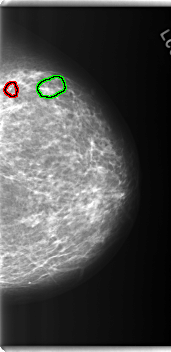

C_0280_1.LEFT_MLO

FILE: C_0280_1.LEFT_MLO.OVERLAY

TOTAL_ABNORMALITIES 4

ABNORMALITY 1

LESION_TYPE MASS SHAPE ARCHITECTURAL_DISTORTION MARGINS SPICULATED

ASSESSMENT 4

SUBTLETY 4

PATHOLOGY BENIGN

ABNORMALITY 2

LESION_TYPE CALCIFICATION TYPE PLEOMORPHIC DISTRIBUTION CLUSTERED

SUBTLETY 5

ABNORMALITY 3

ASSESSMENT 3

ABNORMALITY 4

LESION_TYPE CALCIFICATION TYPE AMORPHOUS DISTRIBUTION CLUSTERED

SUBTLETY 3

LEFT_MLO LINES 5920 PIXELS_PER_LINE 3192 BITS_PER_PIXEL 12 RESOLUTION 50 OVERLAY